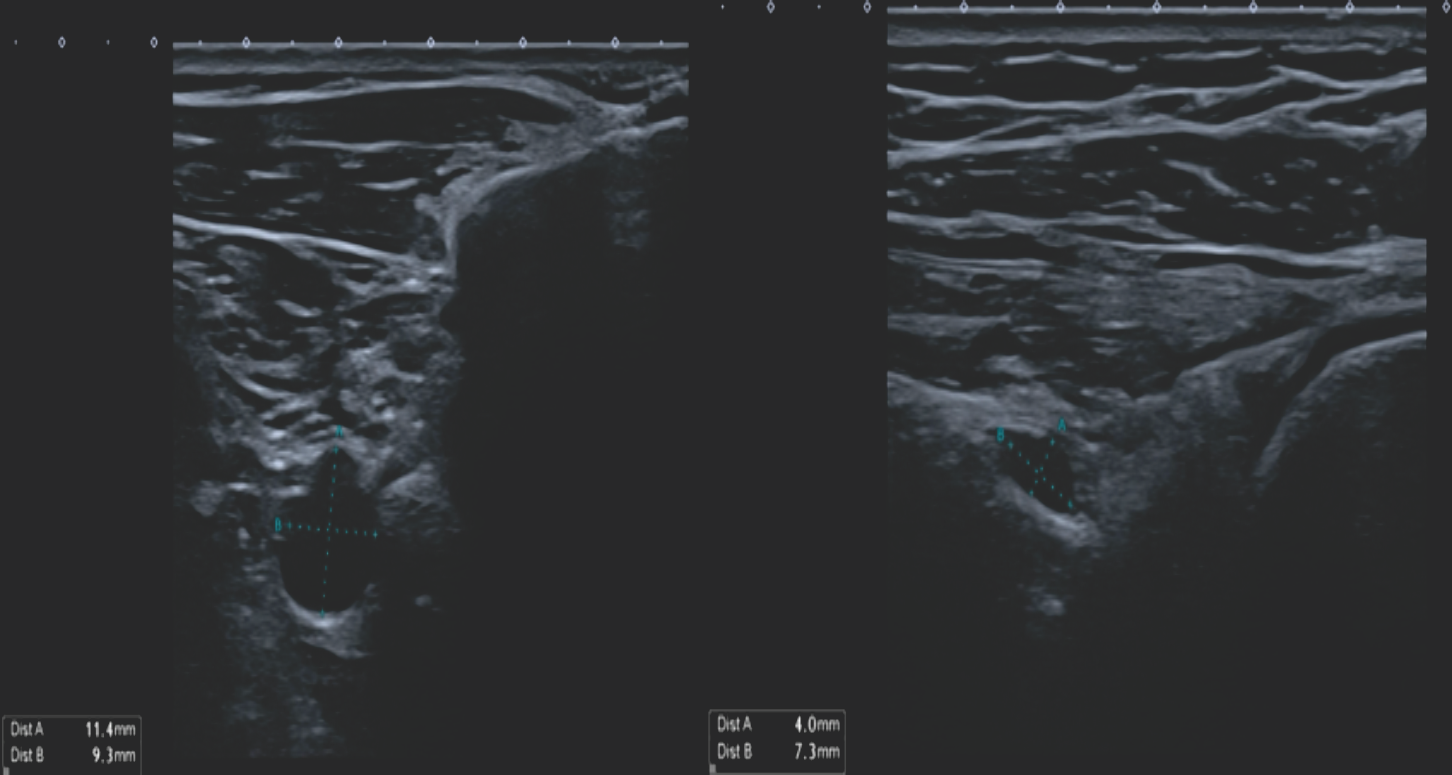

Figure 2: Ultrasound imaging of the right shoulder 3 months after cyst aspiration and intralesional glucocorticoid injection. The cyst shows enlargement at the suprascapular notch (11.4 × 9.3 mm), with a stable size at the spinoglenoid notch (4.0 × 7.3 mm).

A 63-year-old right-handed woman with no relevant medical history presented with a 6-month history of continuous dull right shoulder pain, aggravated by lying on the affected side and associated with nocturnal pain. She reported functional limitations in overhead activities. Analgesics included paracetamol, ibuprofen, and topical diclofenac. Her regular physical activities included walking and cycling. Examination showed normal biceps and triceps reflexes, intact sensation, negative Spurling’s test, and preserved cervical and cervicodorsal mobility with negative facet joint and foraminal compression tests. Increased tone was noted in the postural muscles, mainly in the upper trapezius. Shoulder assessment revealed painless passive external rotation and abduction-external rotation, but active external rotation strength was reduced to 4/5 on the Medical Research Council scale. Impingement signs and Jobe’s test were negative. Palpation over the suprascapular notch elicited tenderness. Ultrasound revealed a cystic lesion posterior to the glenoid. Arthro-MRI confirmed a cyst from the spinoglenoid to the suprascapular notch along the course of the SSN. No teres minor atrophy was observed. Additional findings included insertional tendinopathy of the supraspinatus and a superoposterior labral tear. The imaging appearance was consistent with an intraneural ganglion cyst. Electromyography (EMG) showed a right SSN lesion at or proximal to the supraspinatus muscle branch, consistent with a partial axonotmesis and associated with moderate-to-severe muscular involvement. The patient initially opted for a conservative approach with physiotherapy, ultrasound-guided aspiration, and intralesional glucocorticoid injection for symptomatic relief (Depo-Medrol 80 mg). Aspiration of the cyst was attempted. However, only 1 mL of the thick mucinous fluid could be retrieved. At 4 weeks, pain improved but there was persistent fatigue with overhead activity and weakness in both the supraspinatus and infraspinatus. Ultrasound showed a persistent anechoic, lobulated cyst (9.4 × 7.6 mm) in the suprascapular notch, with extension to the spinoglenoid (4.1 × 7.4 mm) notch, without hyperemia. Physiotherapy was continued, with follow-up planned in 2 months. Two months later, ultrasound showed enlargement at the suprascapular notch (11.4 × 9.3 mm) and a stable size at the spinoglenoid notch (4.0 × 7.3 mm) (Fig. 2). EMG revealed improved compound muscle action potential (CMAP) amplitude and recruitment in the supraspinatus, but decreased recruitment and denervation in the infraspinatus. A surgical indication was made for arthroscopic decompression of the cyst at both the suprascapular and spinoglenoid notches and treatment of the labral tear. Arthroscopy revealed a degenerative type IIB superior labrum anterior to posterior (SLAP) lesion, treated with biceps tenotomy and labral debridement, as repair was deemed infeasible. Cyst decompression exposed a well-defined synovial cyst wall surrounding the nerve. Incision released a wine-red mucinous fluid, and the wall was carefully debrided to achieve complete decompression (Fig. 1)